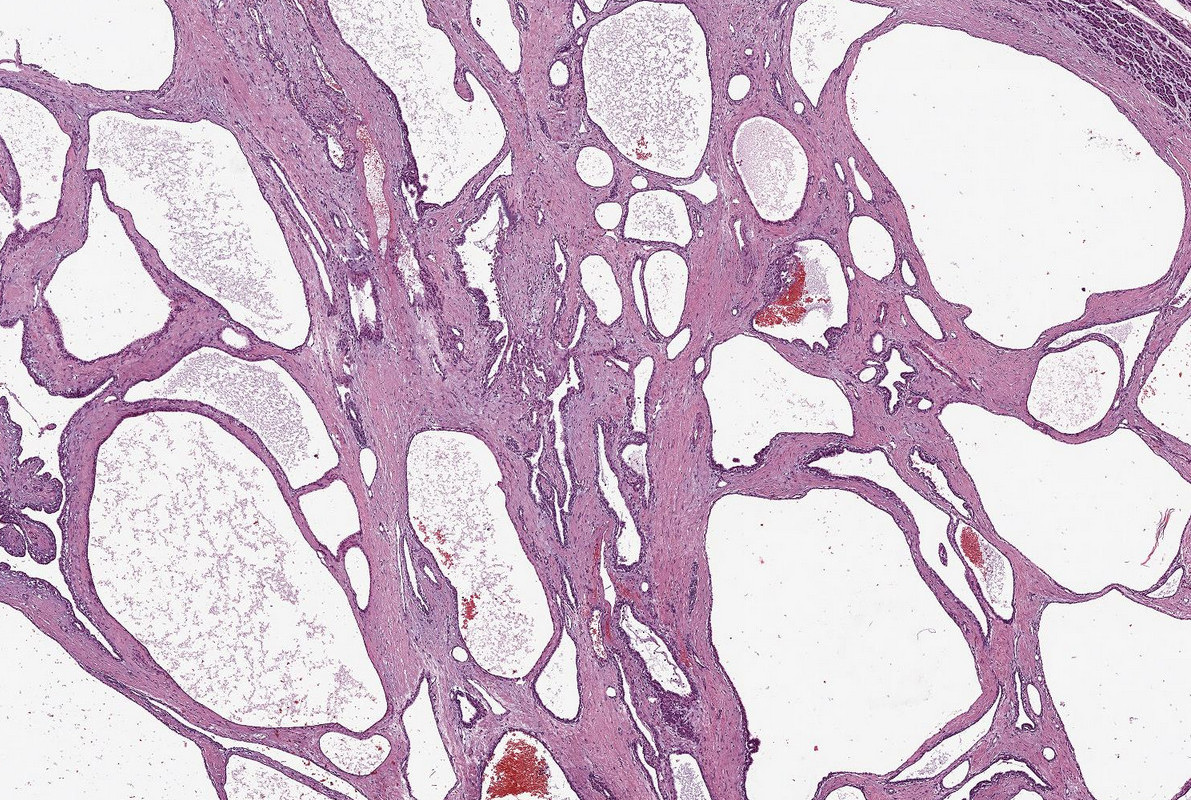

Maßgeschneiderte Transplantationsorgane aus dem Drucker – an dieser Vision arbeiten Wissenschaftlerinnen und Wissenschaftler des KIT. Mit 3D-Bioprinting-Technologien entstehen funktionsfähige Herzklappen, aus patienteneigenen Zellen – schichtweise im 3D-Druck hergestellt und wachstumsfähig. Damit lassen sich Abstoßungsreaktionen vermeiden, Zusatzoperationen bei Kindern reduzieren und mittelfristig auch ganze Organe drucken. Zudem eröffnet die Technologie neue Wege für personalisierte Medikamententests und weniger Tierversuche.